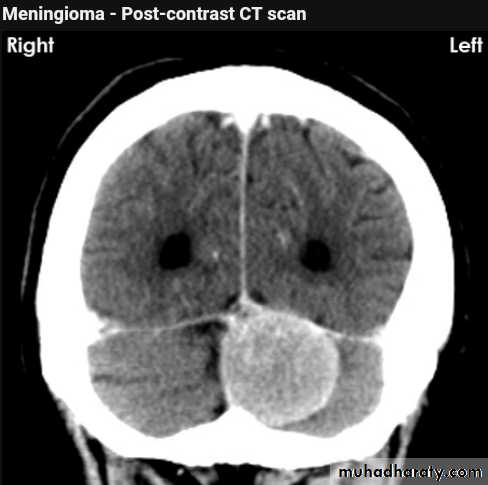

Meningioma

Benign tumor arise from the arachnid cells of the meningeal covering of the brain are most common primary intracranial neoplasm

Usually present in middle age female

it is well defined extra axial , located mainly at the convexity of the skull periphery

CT finding

meningioma presented as isodense area or slightly hyper density area with surrounded crescent of hypo density ( csf cap ) post contrast injection the lesion enhance homogeneously with enhancing Dural tail .

20 % show calcification

hyperostosis & thickening of the near by bony part of the skull & diplioc space .

it may be associated with little or no peri focal edema .

if the lesion associated with central necrosis with large perifocal edema meningio sarcoma should be excluded .